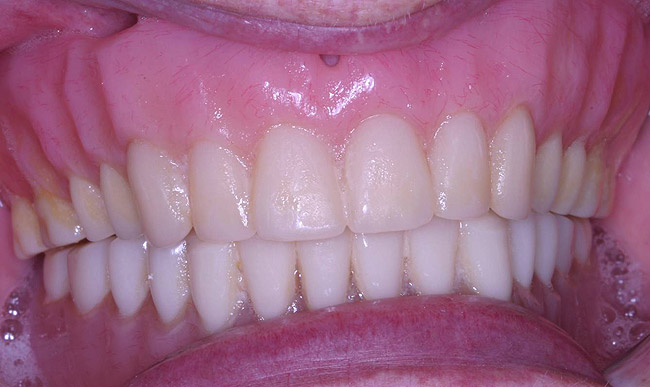

The laboratory then fabricated a light-cured, stabilized base plate on which anterior and posterior teeth were set using the silicone putty mold made previously and waxed up to final contour and delivered to the office. The upper denture was tried in and a visual examination was performed to certify function, esthetics, phonetics, and patient/clinician satisfaction (Figure 14). The denture was sent back to the laboratory for final processing with the Ivocap Denture System (Ivoclar Vivadent North America, Amherst, NY). The prosthesis was trimmed and polished to high luster to prepare for final insertion (Figure 15). Additionally, Massachusetts requires denture labeling with a patient identifier (wearer's name, driver's license number, or Social Security Number, etc) for forensic purposes, and this was exacted according to state law.28

Figure 15  Final case, postoperative.

Figure 15